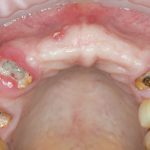

Обычно, через день после операции рана выглядит вот таким образом:

Отёк, болезненные ощущения, затрудненное открывание рта — вполне себе обычная симптоматика после подобных операций. Впрочем, как и после остеопластик другими методами.